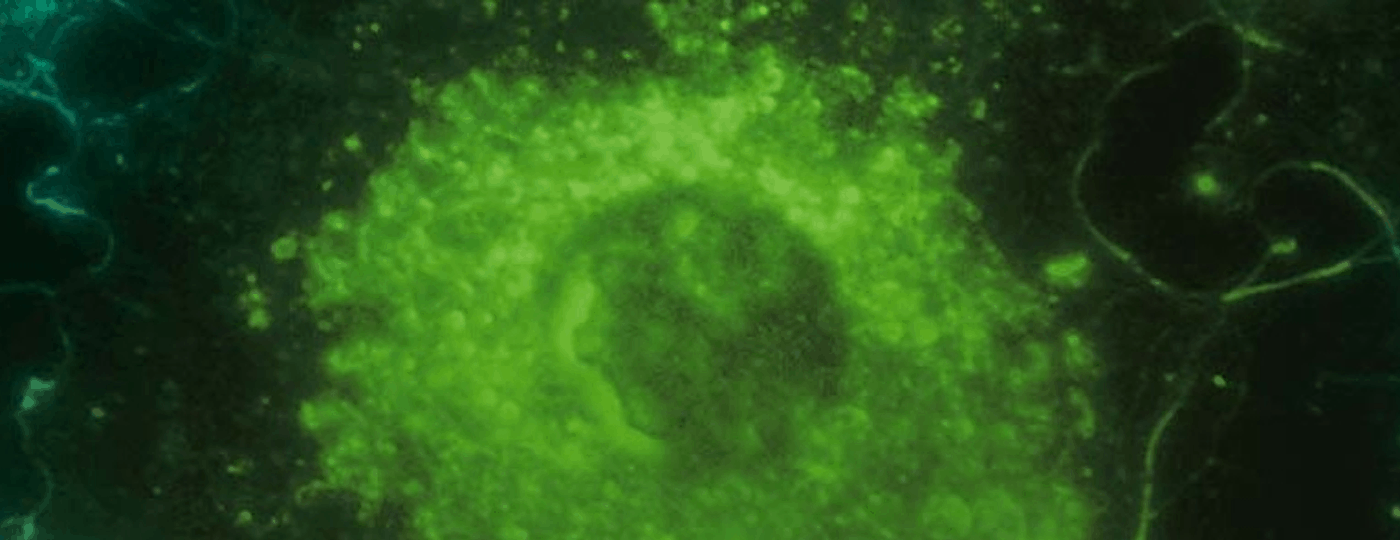

“This antibody is designed to block the activity of an enzyme called CD39, which sits on the surface of harmful inflammatory cells,” Professor Smyth said.

“Blocking CD39 with the antibody releases an extracellular chemical signal called ATP.

“In laboratory tests, we’ve shown that this sets off a chain of events that ultimately kills the cancer-promoting inflammatory cells and releases proteins – called cytokines – that help immune cells called T cells fight the cancer.